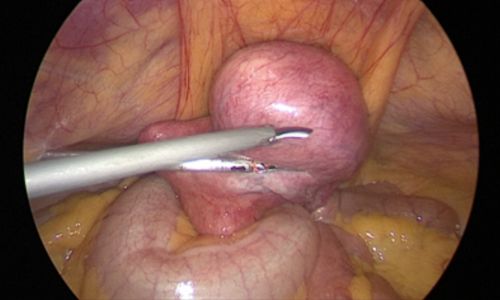

During surgery, no incisions were made on the abdominal wall. The procedure was performed through the natural birth passage using a hysteroscope, which allowed direct visualisation of the uterine cavity. The fibroid was identified & removed using an energy source.

Unlike traditional surgery, no abdominal cuts or stitches are required. A hysteroscope, a thin telescope-like instrument, is inserted through the vagina & cervix into the uterus. The fibroid is directly visualised & removed using an energy source or resectoscope.